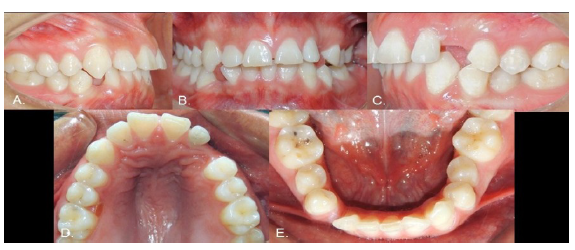

Case 2

Female, 15 years old. As with Case 1, the inferior left canine was the only primary tooth remaining in the mouth (Fig. 3). The radiograph showed that the 3.3 exhibited a type 2 transmigration (Figs. 4, A and B). The tooth was located closer to the mandible edge than in Case 1, precluding the use of orthodontic traction, and it was decided to monitor the tooth. Dental protrusion was the initial reason for the appointment, and the patient requested orthodontic treatment of this condition. Because the 3.3 was far from the roots of the neighboring teeth, the orthodontist decided there would be no risk in moving teeth in this zone. To correct the protrusion, the first premolars were extracted (except for quadrant 3 since the 3.3 was transmigrated). The 3.3 would not be restored in this treatment since the 3.4 would take its place. The 1-year follow-up panoramic x-ray showed no significant changes (Fig. 4C).